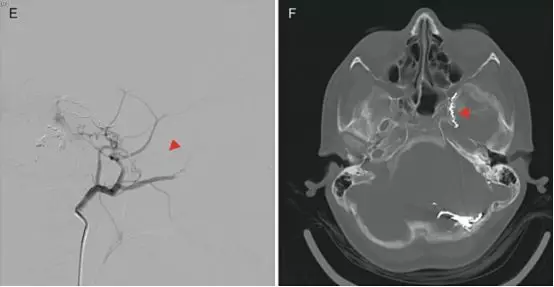

Nam等报道一例60余岁的女性病人,因面肌痉挛入院。造影发现颈内动脉颈段闭塞,通过圆孔动脉重建了颈内动脉颅内段血流。

A,左侧颈总动脉造影,正位,显示左侧颈内动脉起始段闭塞,可见圆孔动脉(箭头)。B,圆孔动脉增粗,走行迂曲,与颈内动脉海绵窦段下外侧干吻合建立侧支循环。